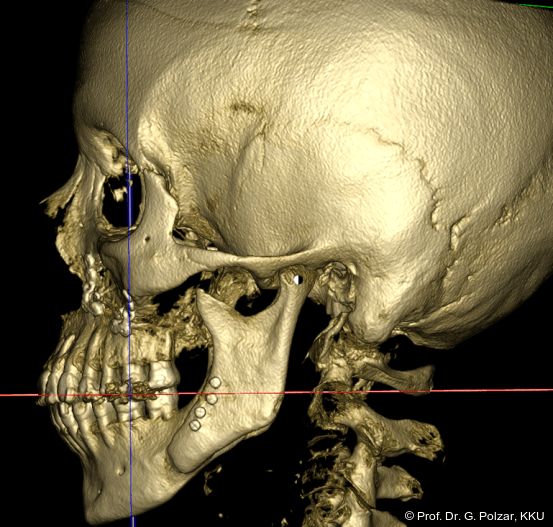

KG-Position: Die 3D-Ansicht im DVT zeigt eine vorverlagerte UK-Position bei neutraler Okklusion (Abb. 4a+b).

Diese deutlich anteriore Gelenkposition im Neutralbiss ließ den Verdacht auf einen Sunday Bite zu. Das heißt, die Patientin schob den Unterkiefer aktiv nach vorne, um damit schönere Schneidezahnkontakte bzw. eine vermeintlich neutrale Okklusion zu erreichen. Nach mühsamen Lockerungsübungen gelang es der Patientin, auch in die zen­trale Kiefergelenkposition zu wechseln. So zeigte sich das ganze Ausmaß der Malokklusion. In neutraler KG-Position hatte die Patientin eine sagittale Frontzahnstufe von ca. 7 mm mit 1 PB Klasse II-Okklusion im Seitenzahn­bereich (Abb.5a+b, 7a–c).

Beide Kiefergelenke (KG) befinden sich nun in zentraler Kondylen-/Fossa-Position bei neu­traler Okklusion (Abb. 10+11).